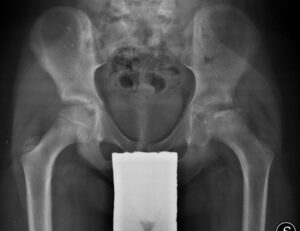

Una radiografia del bacino e dell’anca in proiezione ascellare consentono generalmente di arrivare a una diagnosi di morbo di Perthes nelle fasi conclamate.

- Fase di addensamento: il nucleo femorale appare più denso, “metallizzato”